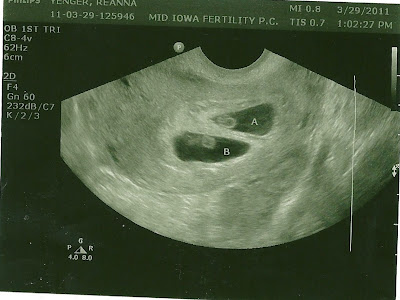

This is the good news:

First HCG (blood pregnancy test) on March 13th: 1175!

Second HCG on March 15th: 3067!

First Ultrasound March 29th showed this:

IT'S TWINS!!!

We heard both heartbeats! Baby A: 122 Baby B: 132

Second Ultrasound April 12th: Baby A: 170 Baby B: 178

Baby A was moving his/her arms and legs and Baby B was shimmying all over - SO AMAZING! We also "graduated" from the fertility doctor to my regular OB/GYN today.

This is the good news:

First HCG (blood pregnancy test) on March 13th: 1175!

Second HCG on March 15th: 3067!

First Ultrasound March 29th showed this:

IT'S TWINS!!!

We heard both heartbeats! Baby A: 122 Baby B: 132

Second Ultrasound April 12th: Baby A: 170 Baby B: 178

Baby A was moving his/her arms and legs and Baby B was shimmying all over - SO AMAZING! We also "graduated" from the fertility doctor to my regular OB/GYN today.